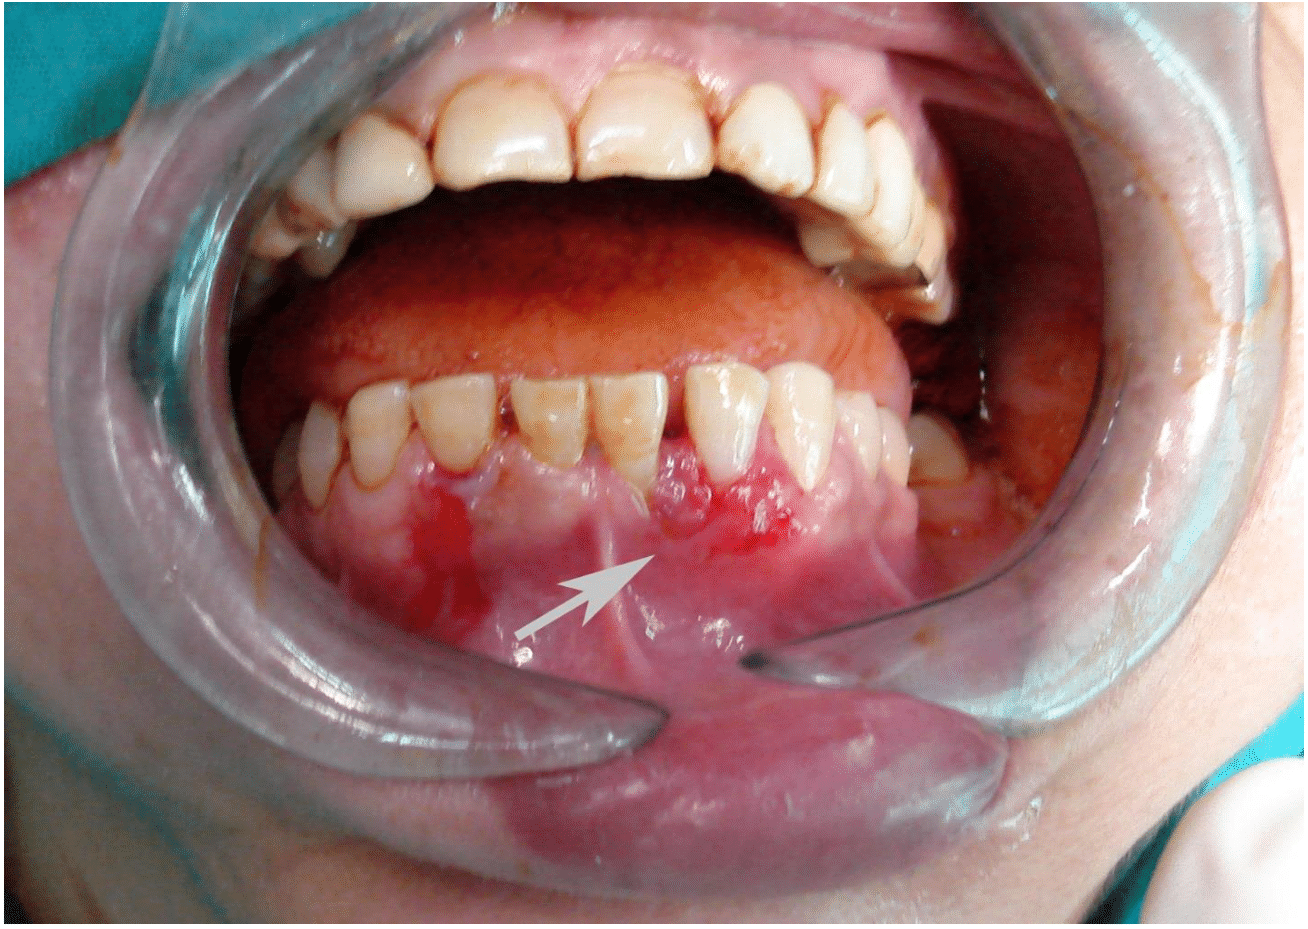

A healthy 50-year-old female patient was referred for evaluation of gingival lesion related to lower left central and lateral incisor teeth (Figure 1). The clinical impression from the referring clinician was a localized gingival inflammation. According to the patient's description, she had found the painless lesion over the lower left anterior teeth one week previous. The lesion of the gingiva not responded to the regular care and local treatment for two weeks. The patient medical and family histories were noncontributory. An Incisional biopsy was performed and read as well-differentiated squamous cell carcinoma (Grade I).

Figure 1 Intraoral clinical presentation of gingival SCC.

A comprehensive history was taken including the demography, past medical history, and dental and social history (tobacco and alcohol habits) was free. This was followed by a detailed examination that recorded the site of lesion, size of lesion, type of lesion (ulcerated, infiltrative, proliferative, or combination) and a detailed examination of the neck for lymph node involvement. Ulcerative lesion of the marginal gingiva related to lower left lateral incisor about 5 X 5 mm was observed. No lymph nodes involvement was noticed.